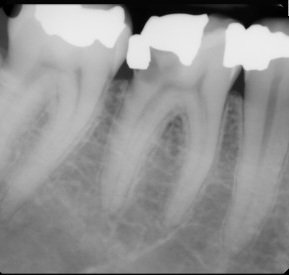

Infected Molar

Patient: Maria T., 38